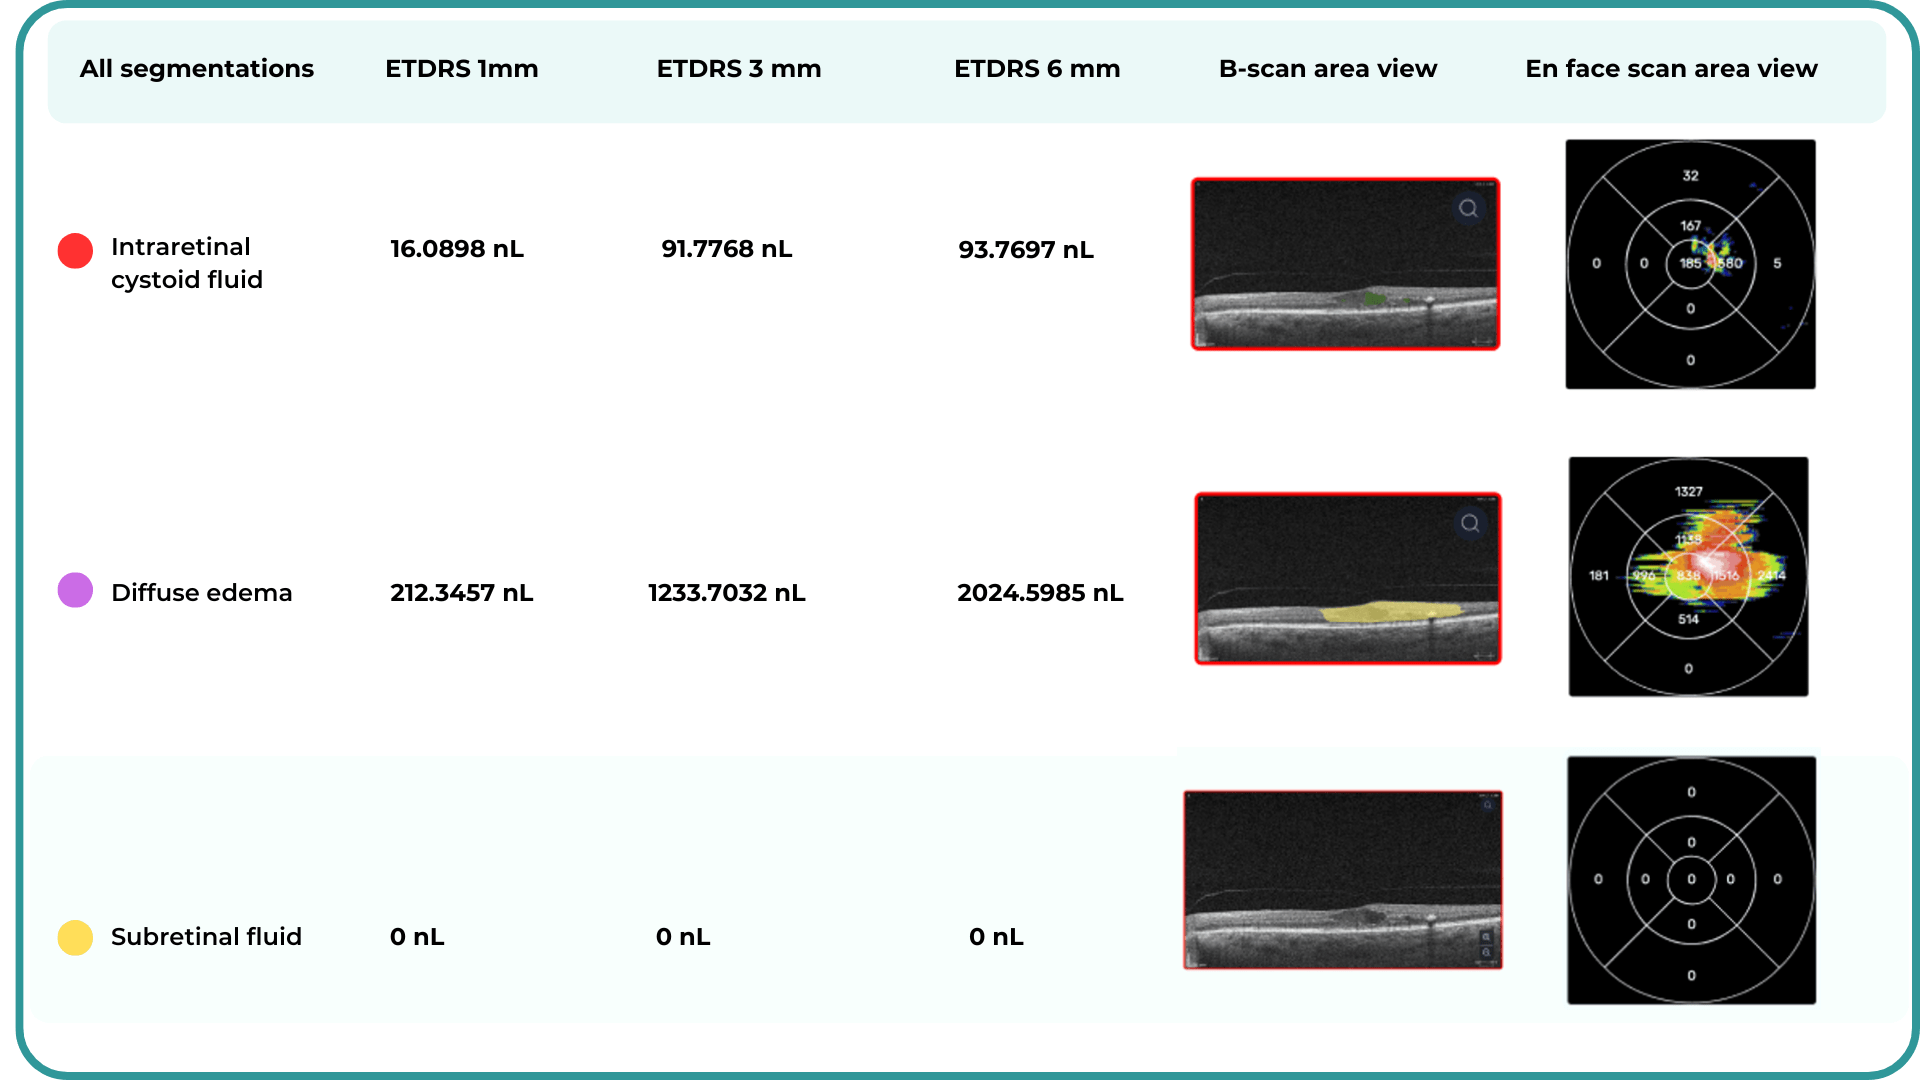

Imaging biomarkers are a particularly attractive option for clinical practice due to their non-invasive and real-time nature. Quantitative measurements of retinal thickness, fluid volume, and other biomarkers relevant to diseases like diabetic retinopathy and age-related macular degeneration aid in treatment monitoring.

OCT reports with customized measurements and selected biomarkers, retinal layers, or segments allow for precise focus on treatment monitoring and patient response to therapy. This personalized approach enhances clinical decision-making by highlighting each case’s most relevant information.

In ophthalmology, AI-powered analysis of OCT scans can provide precise, quantitative measurements of retinal thickness, fluid volume, and other biomarkers relevant to diseases like diabetic retinopathy and age-related macular degeneration. These measurements can aid in diagnosis, disease staging, treatment monitoring, and prediction of treatment response.

Systems like Altris for pathology detection and segmentation enabled automated disease characterization and longitudinal monitoring of therapeutic response in AMD. Multiple studies have demonstrated the value of volumetric fluid characterization, compartment-specific OCT feature evaluation, and subretinal fibrosis and hyperreflective material quantification.

The extraction of quantitative fluid features and assessment of retinal multi-layer segmentation from OCT scans have offered valuable insights into disease prognosis and longitudinal dynamics of Diabetic Retinopathy.

A recent study demonstrated that quantitative improvement in ellipsoid zone integrity following anti-VEGF therapy for DME significantly correlated with visual function recovery. Furthermore, novel imaging biomarkers, such as the retinal fluid index (RFI), are emerging as tools for precisely monitoring treatment response. Studies have shown that early RFI volatility can predict long-term instability in visual outcomes after treatment.